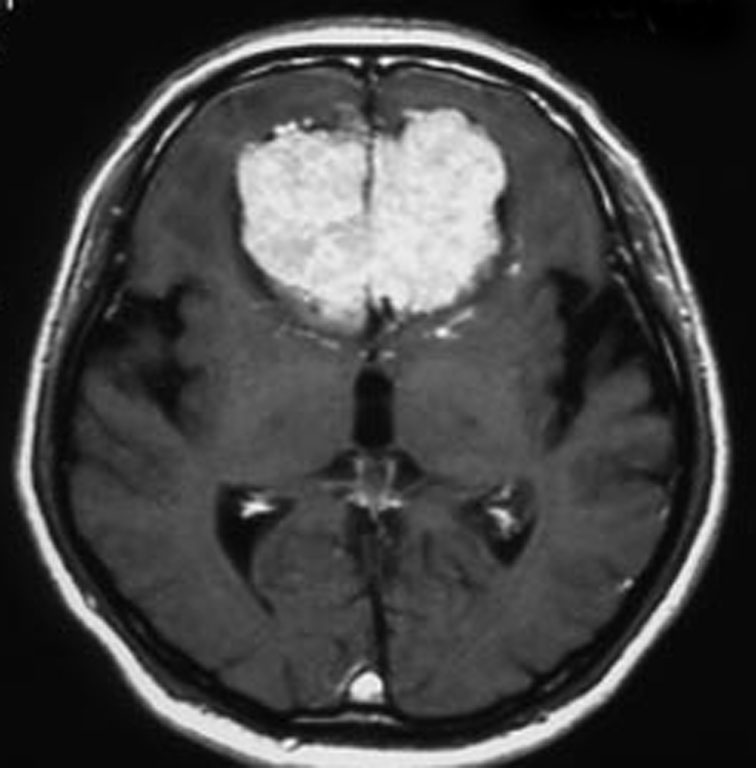

上矢状洞髄膜腫 superior sagittal sinus meningioma

上矢状洞を埋め尽くすように増大して,頭蓋骨浸潤が著しい髄膜腫ですが,ごく軽度の右足脱力以外に何の症状もありません。上矢状洞はゆっくり閉塞すれば,このような頭頂部から後頭部にわたる広範閉塞でも,静脈還流に障害がない場合が多いといえます。大脳の前半部の血流は前頭葉表面の皮質静脈から海綿静脈洞に側副路を形成しています。頭蓋内圧亢進所見もなく,これらはこの髄膜腫がゆっくり増大したということを示唆しています。

手術直後の画像です。全部いっぺんに摘出するのは無理なので,まず前から80%くらいの腫瘍を摘出しました。肥厚した骨はチタンプレートで置き換えてあります。後頭部の上矢状洞内と大脳鎌に少し残りましたが,この6ヶ月後に2回目の開頭術をして全摘出しました。結果的にこの例では,上矢状洞を冠状縫合のあたりから,静脈洞交会まで壁ごと全部摘出しましたが,脳浮腫も何も生じませんでした。腫瘍の両側にある皮質静脈 cortical veinsを損傷しないことが肝要です。

右の病理像は,頭蓋骨浸潤している部分 ですが,骨破壊は良性髄膜腫に特徴的な骨内浸潤像です。この骨浸潤像は悪性像とはいえません。MIB-1は高いところで8%、低いところで3%程度です。